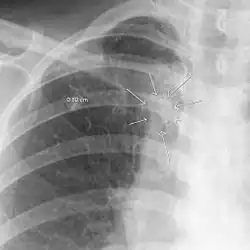

The arrows denote an ill-defined nodular opacity in medial aspect of right upper lobe with ill-defined rim of lucency surrounding it

Differential diagnosisAspergilloma